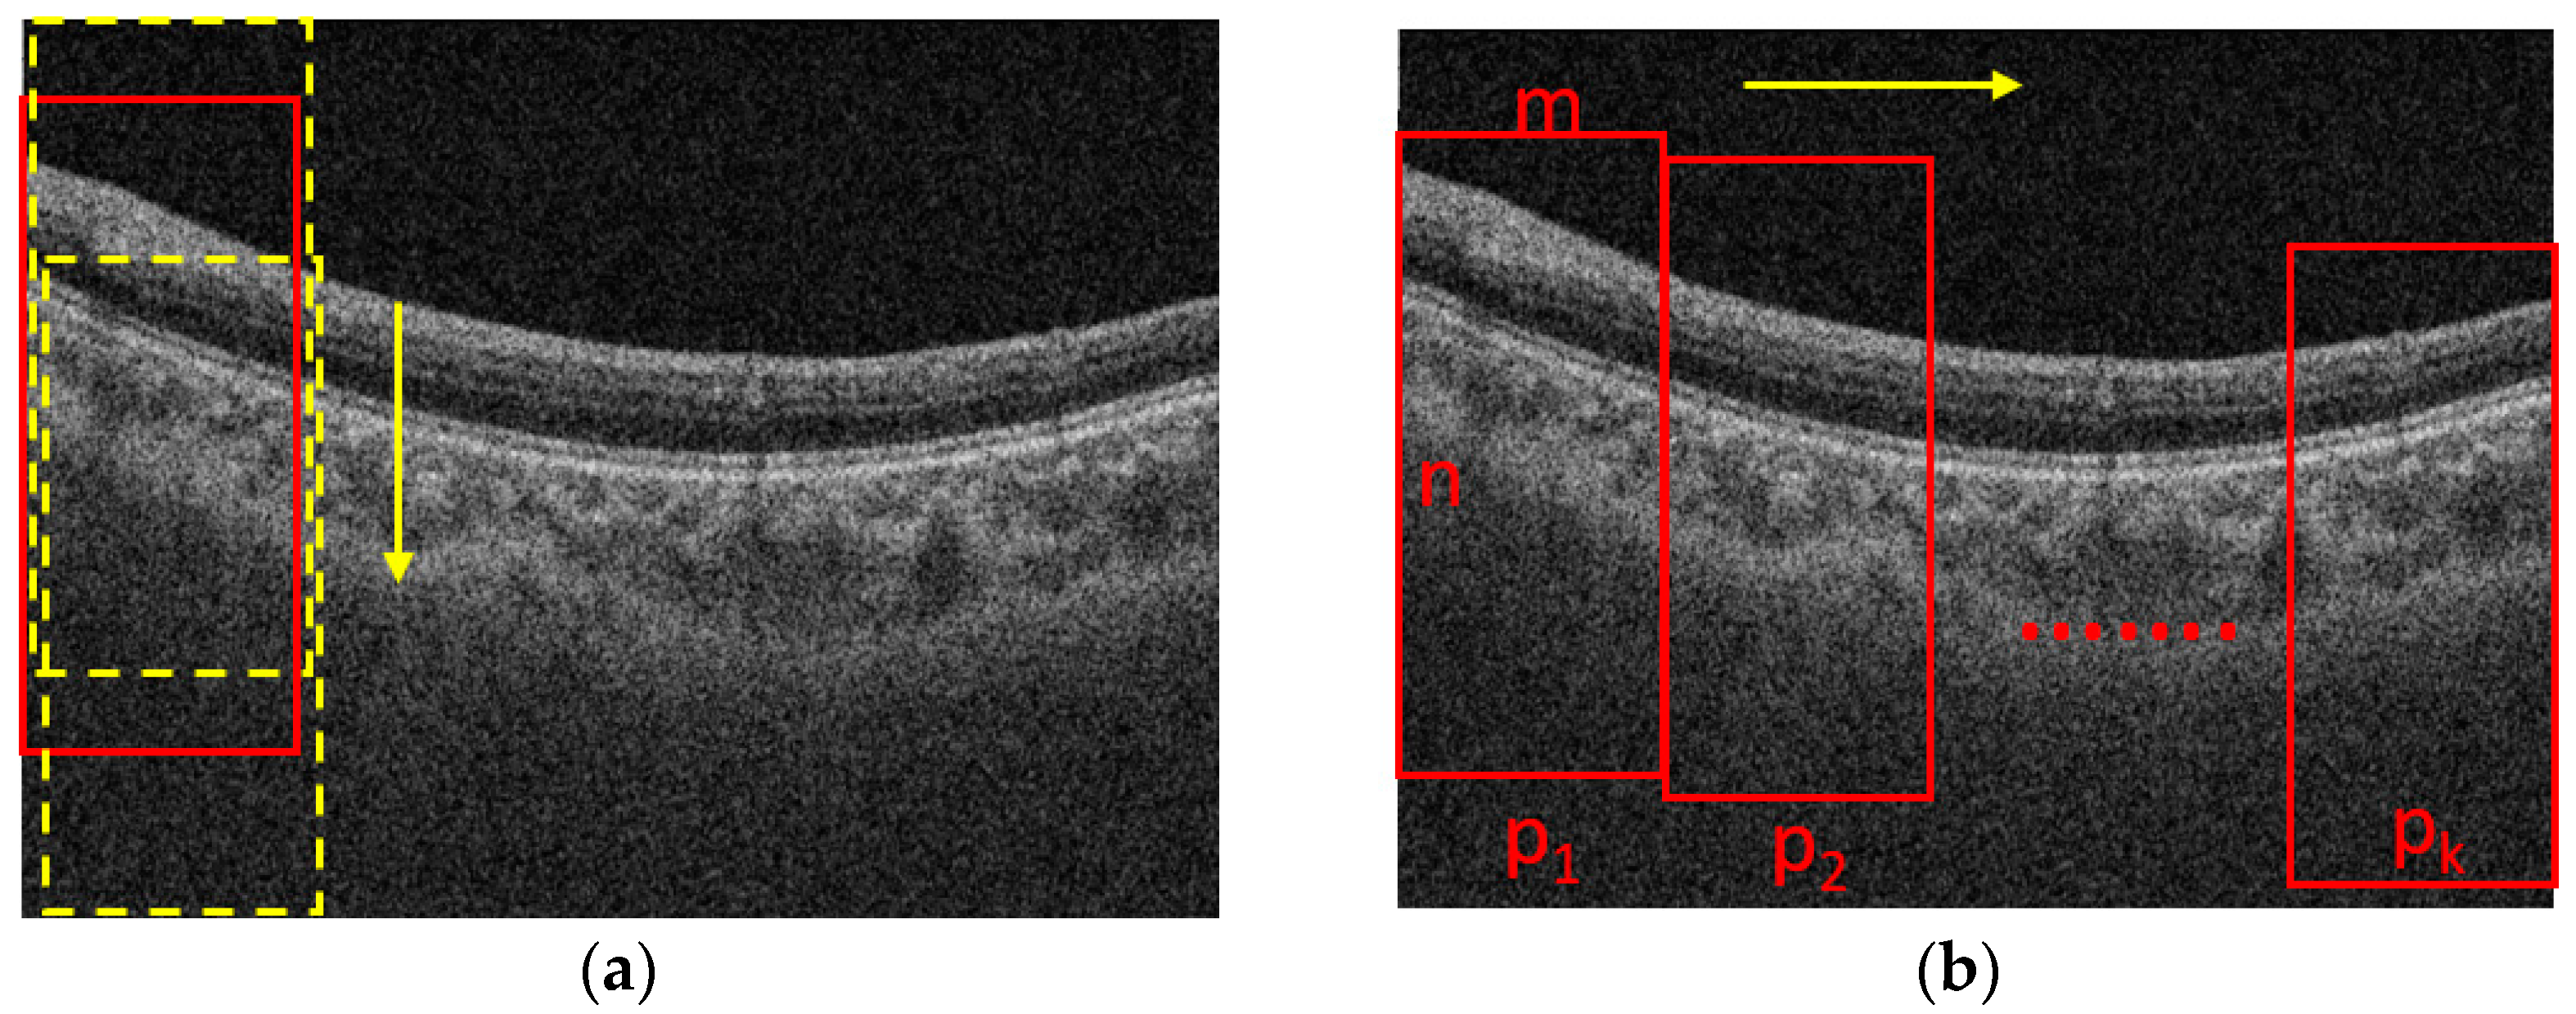

The process for cropping the images is shown in Figure 2. Assume that the size of a B-scan image is N × M, where N is the height and M is the width of the B-scan image, respectively. The B-scan image is first divided into K segments in horizontal direction equally. The width of a patch is m = M/K. The height of a patch is n (n < N), which is set based on the rule that the patch should contain the foreground while excluding the background as much as possible. To determine the location of a patch in the vertical direction, we slide the window with a size of n × m from top to end in a B-scan image with a fixed stride, e.g., 10 pixels, as shown in Figure 2a, and the one with maximal summed intensity is selected as the final patch. Then, we slide the window into the next patch with the stride of m in the horizontal direction, as shown in Figure 2b, and repeat the process shown in Figure 2a. The process shown in Figure 2b is also repeated until the window reaches the rightmost side of the B-scan. It is worth noting that there is no intersection between two adjacent patches, so it is convenient for us to take the average choroidal thickness on each patch to compute the mean thickness of the choroid in the whole B-scan.

Figure 2.

The process for cropping images. (a) sliding in the vertical direction; (b) sliding in the horizontal direction. m and n are the width and height of a patch p respectively.